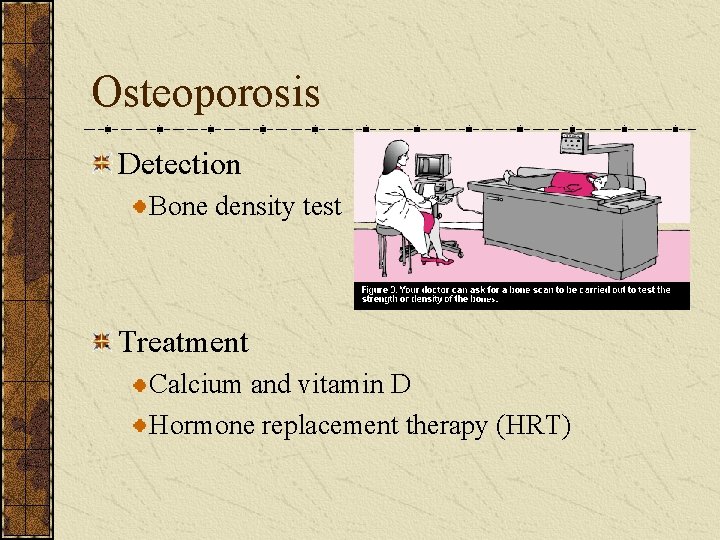

Osteoporosis Disease in which bones become fragile and more likely to break Symptoms none

Prevention=Ca 4 - 8 years old 800 mg 8 -18 years old 1300 mg 19 -50 years old 1000 mg 51 years and older 1200 mg

Osteoporosis Detection Bone density test Treatment Calcium and vitamin D Hormone replacement therapy (HRT)